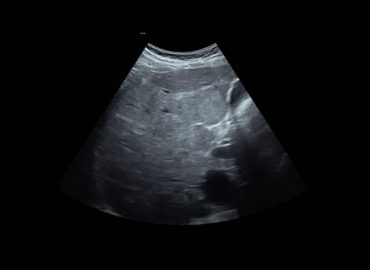

Paciente masculino de 47 años con antecedente de trasplante renal. Consulta a la guardia refiriendo cefalea de 48 hs de […]